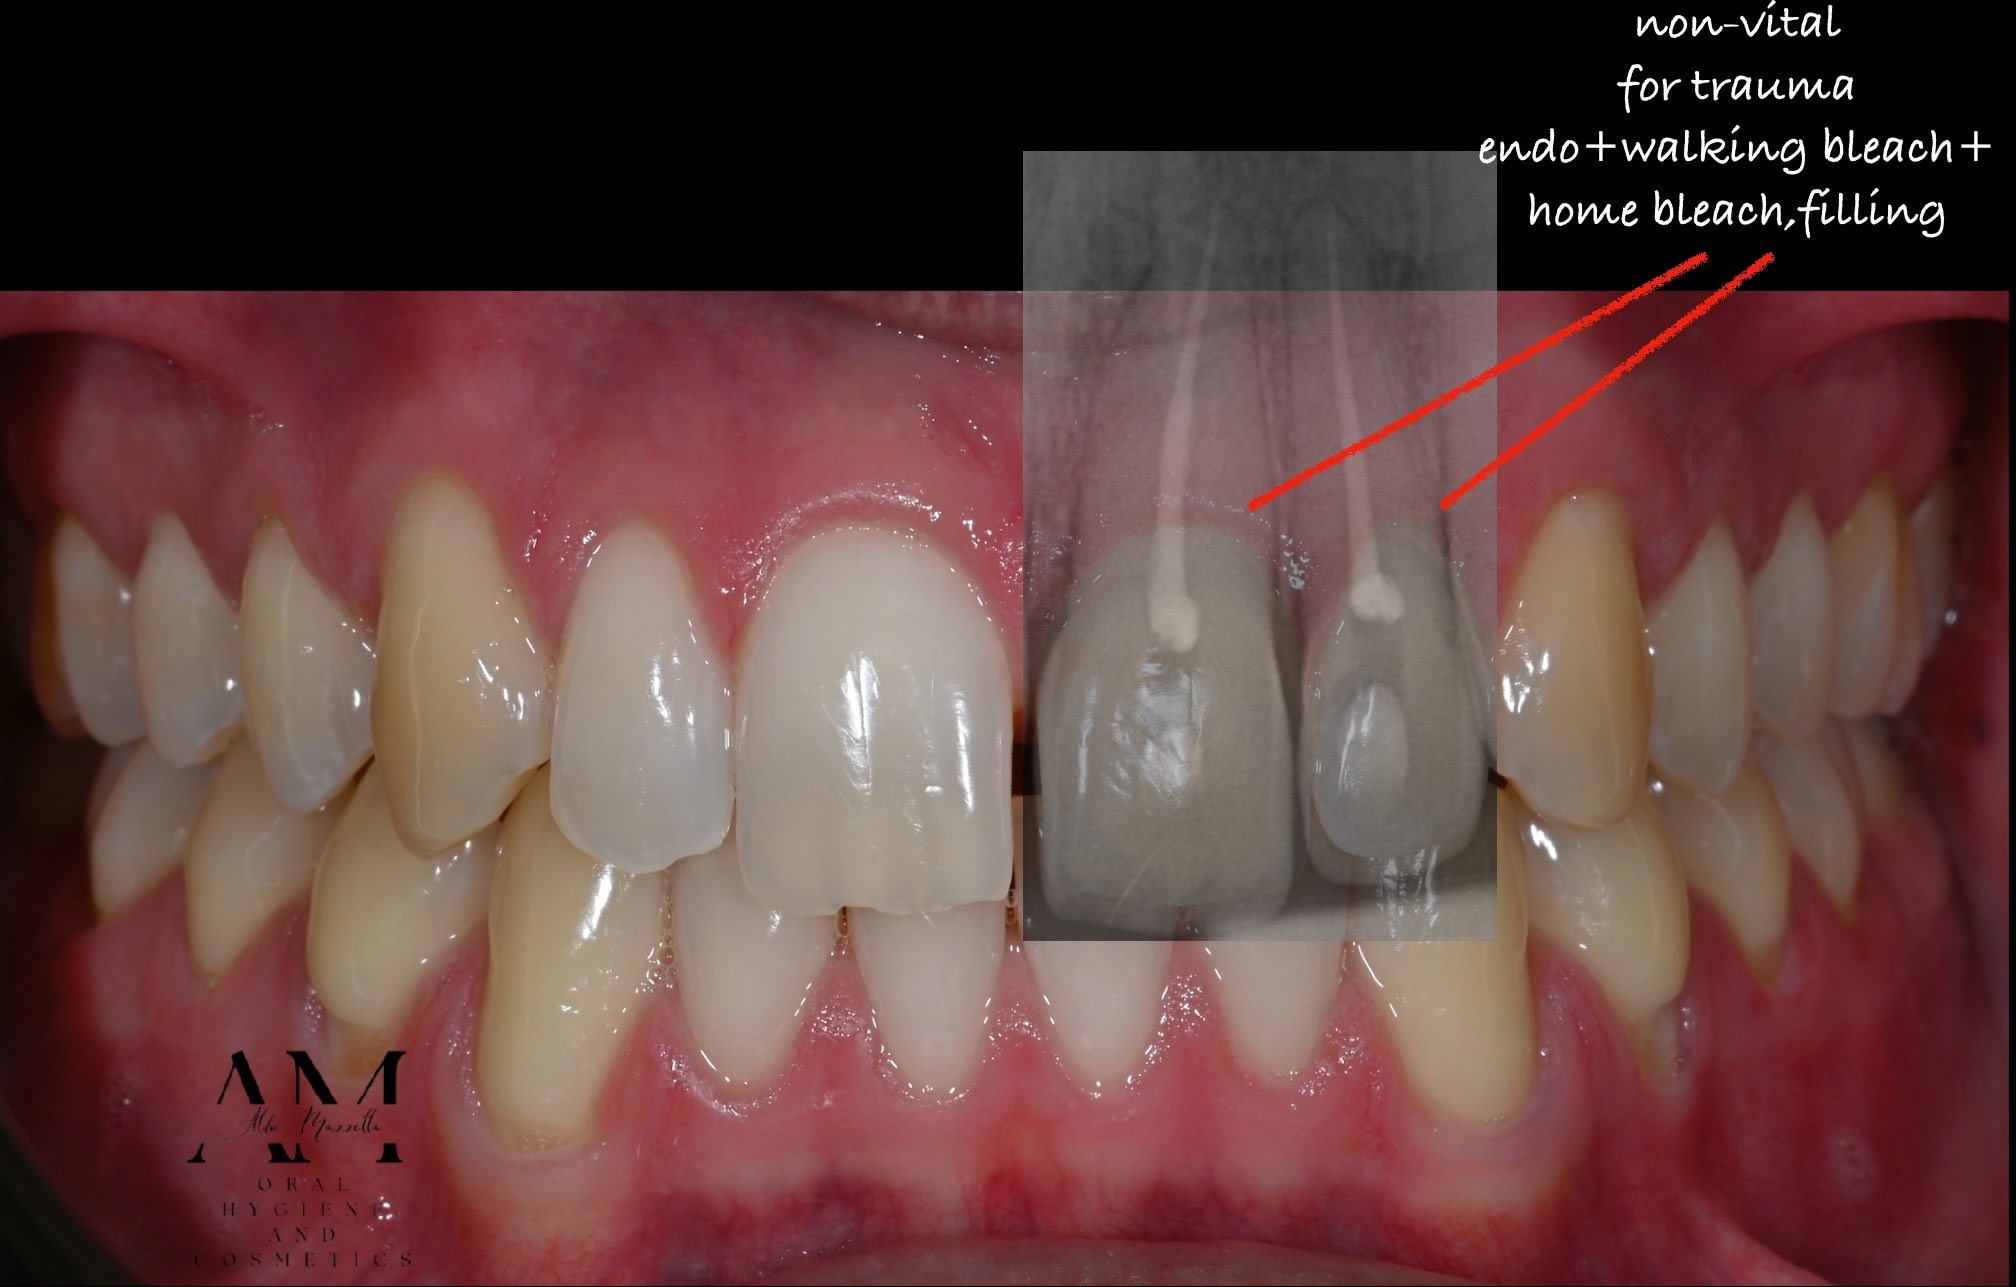

Coloration multicolore suite à un traumatisme sur 2.1 et 2.2. Approche micro-invasive par technique hybride : walking bleach interne + éclaircissement ambulatoire externe. Résultat stable, sans prothèse.

Un patient se présente en consultation pour une coloration multicolore marquée du secteur antérieur supérieur, consécutive à un traumatisme par chute ayant entraîné la dépulpation des dents 2.1 et 2.2. Les traitements endodontiques ont été réalisés avec succès, mais la pigmentation résiduelle — caractéristique des dents non vitales — compromet l'esthétique du sourire.

Le patient exprime une préoccupation esthétique claire, tout en souhaitant éviter toute solution prothétique invasive et coûteuse. L'approche thérapeutique doit donc être à la fois conservatrice, efficace et respectueuse de la structure dentaire résiduelle.

Ce cas illustre la puissance d'une approche pluridisciplinaire structurée : endodontiste, hygiéniste et praticien travaillant en synergie, dans le respect des temps biologiques. La technique hybride BlancOne (ULTRA 35% HP + Night 12% PC) offre une solution conservatrice, reproductible et esthétiquement compétitive face à la prothèse dans les cas de coloration post-traumatique.